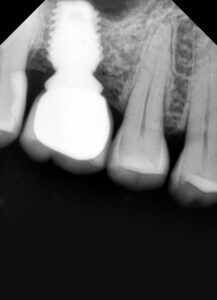

પ્રથમ મુલાકાતમાં ડેન્ટિસ્ટ તમારા મોના દાંત , પેઢા અને જડબા ના હાડકા નું ચેક -અપ કરશે . ડેન્ટિસ્ટ તમારા CBCT (જડબાનું સીટી સ્કેન) જોશે આ હાડકાની રચના અને ઘનતાને સમજવામાં મદદ કરશે જ્યાં ડેન્ટલ ઇમ્પ્લાન્ટ કરવામાં આવશે.

અમારી હોસ્પિટલ માં કરેલ ડેન્ટલ ઇમ્પ્લાન્ટ ના ફોટો

બીજા તબક્કામાં ઇમ્પ્લાન્ટ મૂકવામાં આવે છે.